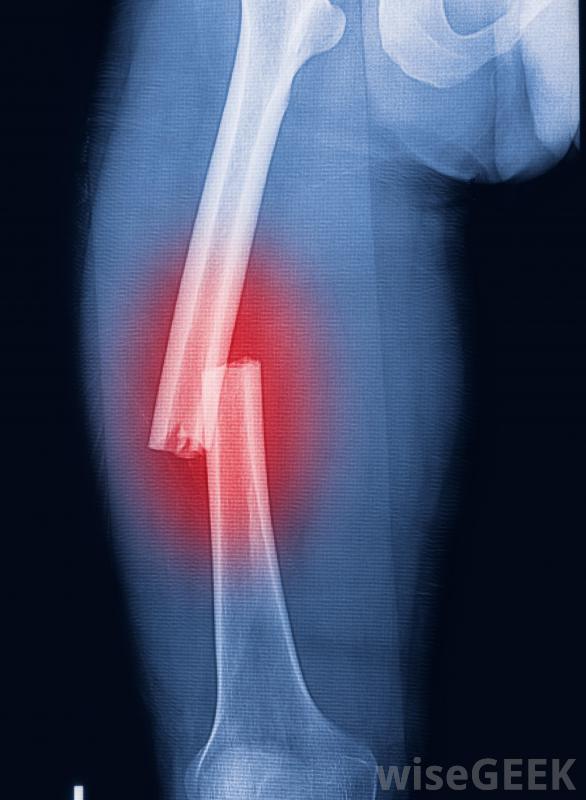

随着年龄的增长,骨骼变得更加脆弱,更容易断裂暴露于辐射是另一个危险因素,这是宇航员最常担心的问题,因为尽管有防护罩,但宇航员在太空工作时辐射水平很高航天员经常被评估是否有低骨密度的迹象,他们在太空中的时间是定量的,以减少与辐射接触有关的永久性损伤的风险。在有辐射的环境中工作的人也会受到高辐射照射的监测白种人和亚洲人天生就有低密度的危险。生活方式导致低骨密度的原因包括运动受限、吸烟,过度饮酒。饮食也是一个因素。饮食失调和营养不良使人们更难形成和保持骨骼。此外,某些药物也可能导致骨密度的下降。随着年龄的增长,他们的骨骼往往比身体重建骨骼的速度要快。这一过程可能会因某些肌肉骨骼疾病而加速。患有骨骼和关节疼痛、肌肉无力和疲劳的人可能需要评估骨骼的医疗状况。如果担心骨密度低,建议服用膳食补充剂和物理疗法来维持骨骼强度,并随着时间的推移重建骨骼。骨密度的降低是一个严重的问题。患者严重骨折的风险增加,尤其是像臀部这样的主要骨骼,骨折后愈合需要更长的时间,也会出现骨痛和虚弱,使日常活动困难,活动受限。